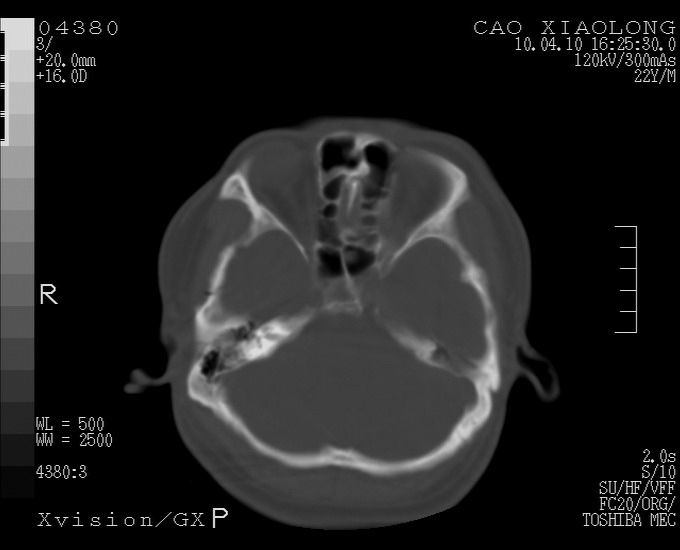

以下是引用随光逐影在2010-4-11 11:00:00的发言:[br]1)左侧额颞顶部硬膜下血肿。2)蛛网膜下腔出血。3)右侧颞顶部颅骨线形骨折。[br][br]20小时后复查:左侧额颞叶脑挫裂伤;左侧额颞顶部硬膜下血肿及蛛网膜下腔出血有吸收表现;右侧颞顶部颅骨线形骨折。[br]